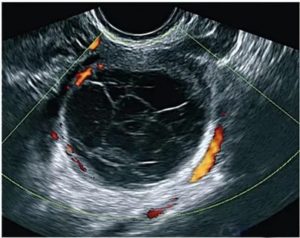

Киста желтого тела

В норме, в фазу угасания желтого тела (если оплодотворение не произошло), железа уменьшается в размере, замещая гранулезные клетки рубцовой тканью.

Рубец, сформированный на поверхности яичника, постепенно рассасывается, придавая яичнику характерный «неровный» вид.

Киста желтого тела образуется из нерегрессировавшей своевременно железы, в которой происходят гипертрофические процессы, вследствие накопления внутриклеточной жидкости. Размеры кисты, как правило, не превышают 8 см.

Основными причинами развития кисты считаются гормональные нарушения и нарушения кровообращения в яичнике. Поскольку в норме серозное содержимое фолликула должно рассасываться по кровеносным сосудам, увеличение его объемов в тканях железы свидетельствует или о повышенной продукции межклеточной жидкости или нарушении лимфооттока.

При проведении УЗИ, кисту желтого тела можно увидеть как анаэхогенное образование округлой формы, имеющее однородную консистенцию и диаметр от 40 до 80 мм. Характерным отличием этой кисты от опухолевых кист яичника, является способность к саморассасыванию, что и происходит в 90% случаев по истечении 2-3 месяцев.

Если киста имеет небольшие размеры и не сопровождается какими-либо симптомами, пациентка должна регулярно делать УЗИ и посещать гинеколога. При отсутствии регрессии со стороны новообразования по истечении двух или трех месяцев, может быть применена медикаментозная или физиотерапия, направленная на стимулирование рассасывания кисты.

Важно! При обнаружении кисты желтого тела во время УЗИ при беременности, проведение терапевтических мероприятий не требуется, так как она не является угрозой для вынашивания плода и исчезает в положенные сроки.